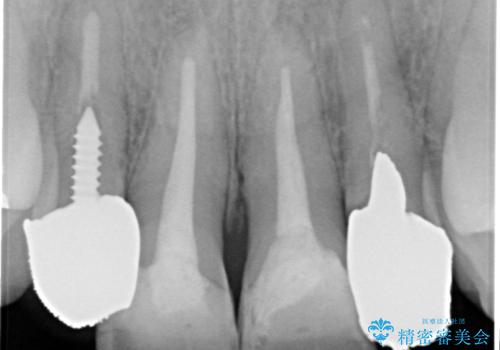

- 「黒ずんで、見栄えの悪い前歯をきれいにしたい。」と、前歯のセラミック治療を希望され来院されました。

全て根管治療のすでになされている歯の変色で、オールセラミッククラウンによる審美性の改善を計画します。

- 52.8万円(ジルコニアクラウン×4・仮歯×4)費用は治療当時の料金となります